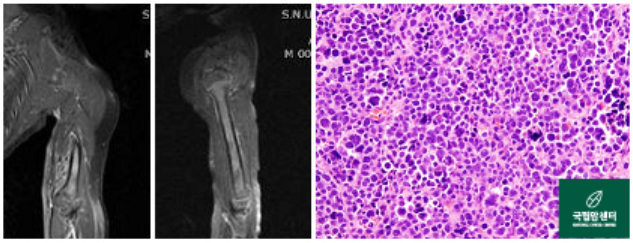

[ 왼쪽 상완부에 횡문근육종을 가진 환아의 사진 ]

[ 위 환아의 항암약물치료 후 사진과 병리 사진 ]

[ 왼쪽 무릎관절 주위에 발생된 활막육종 환자의 사진 ]

[ 왼쪽 대퇴부의 악성말초신경초종 환자의 절단술 전후 사진 ]